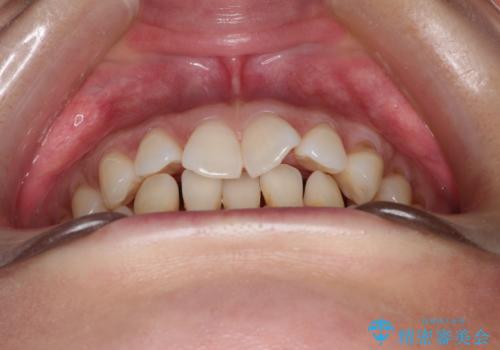

- 上顎の前歯のがたつきと、下の前歯の隙間を主訴に来院されました。

下の前歯が先天的に欠損していました。

上顎の歯と歯の間をわずかに削りスペースを作り、ガタガタの改善し、下顎の前歯は隙間を閉じる計画としました。

非常に協力的な患者様でしたので、早期に治療が終了することができました。